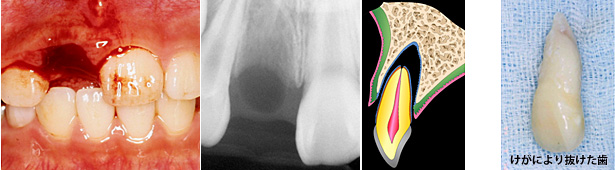

学校にて10歳の女の子の歯がけがで抜けました。養護の先生が抜けた歯をすぐに牛乳につけ、生徒さんを歯医者に連れて行きました。けがで抜けた歯が助かるかどうかは、歯についている歯根膜が生きているかどうかにかかっています。

歯医者さんでは、検査を行った後すぐに歯を戻す治療(再植)を普通は行います。この患者さんの抜けた歯は歯根の先が閉じていましたので、再植2週間後に歯の神経(歯髄)をとる治療が行われました。8年後でも再植された歯はまったく問題がありません。